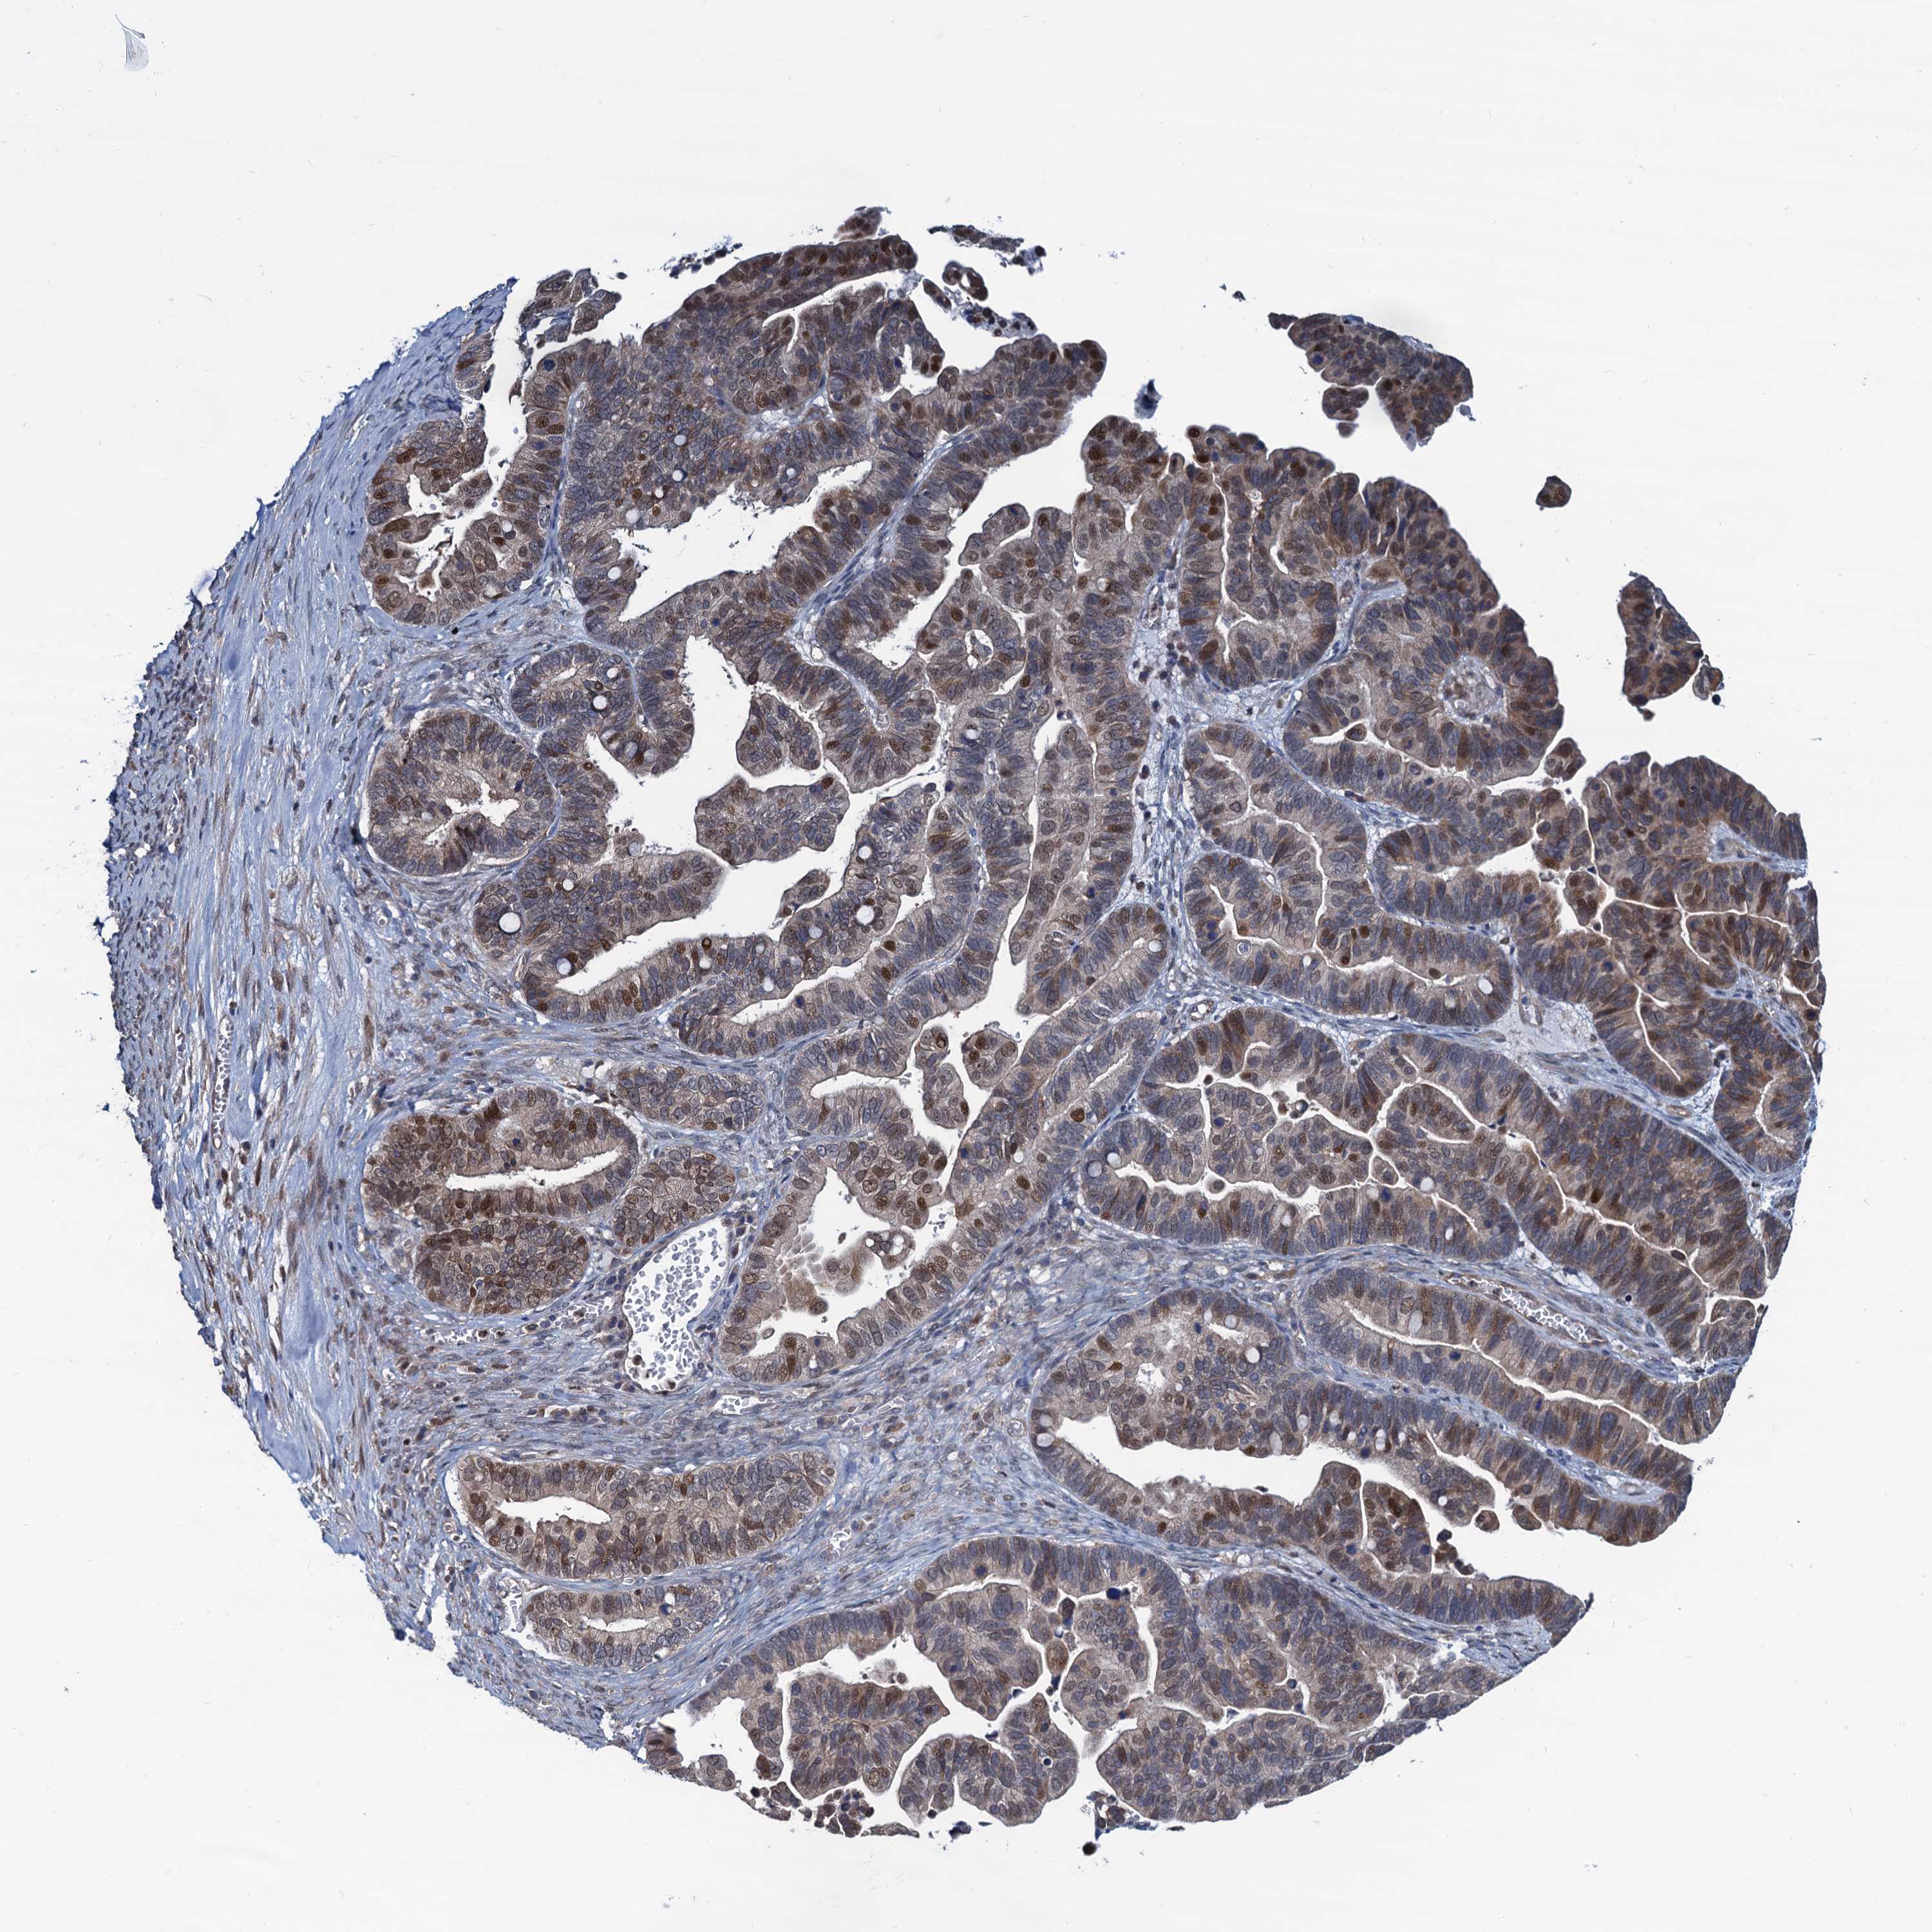

OVARIAN CANCER - Protein expressioni

A mouse-over function shows sample information and annotation data. Click on an image to view it in a full screen mode. Samples can be filtered based on level of antibody staining by selecting one or several of the following categories: high, medium, low and not detected. The assay and annotation is described here.

Note that samples used for immunohistochemistry by the Human Protein Atlas do not correspond to samples in the TCGA dataset.

Antibody stainingi

Antibody staining in the annotated cell types in the current human tissue is reported as not detected, low, medium, or high, based on conventional immunohistochemistry profiling in selected tissues. This score is based on the combination of the staining intensity and fraction of stained cells.

Each image is clickable and will lead to virtual microscopy that enables deeper exploration of all samples and also displays staining intensity scores, fraction scores and subcellular localization as well as patient and tissue information for each sample.

Antibody HPA041514

Staining

High

Medium

Low

Not detected

Intensity

Strong

Moderate

Weak

Negative

Quantity

>75%

75%-25%

<25%

None

Location

Nuclear

Cytoplasmic/membranous

Cytoplasmic/membranous,nuclear

Cystadenocarcinoma, serous, NOS

Carcinoma, endometroid

Cystadenocarcinoma, mucinous, NOS

Carcinoma, NOS